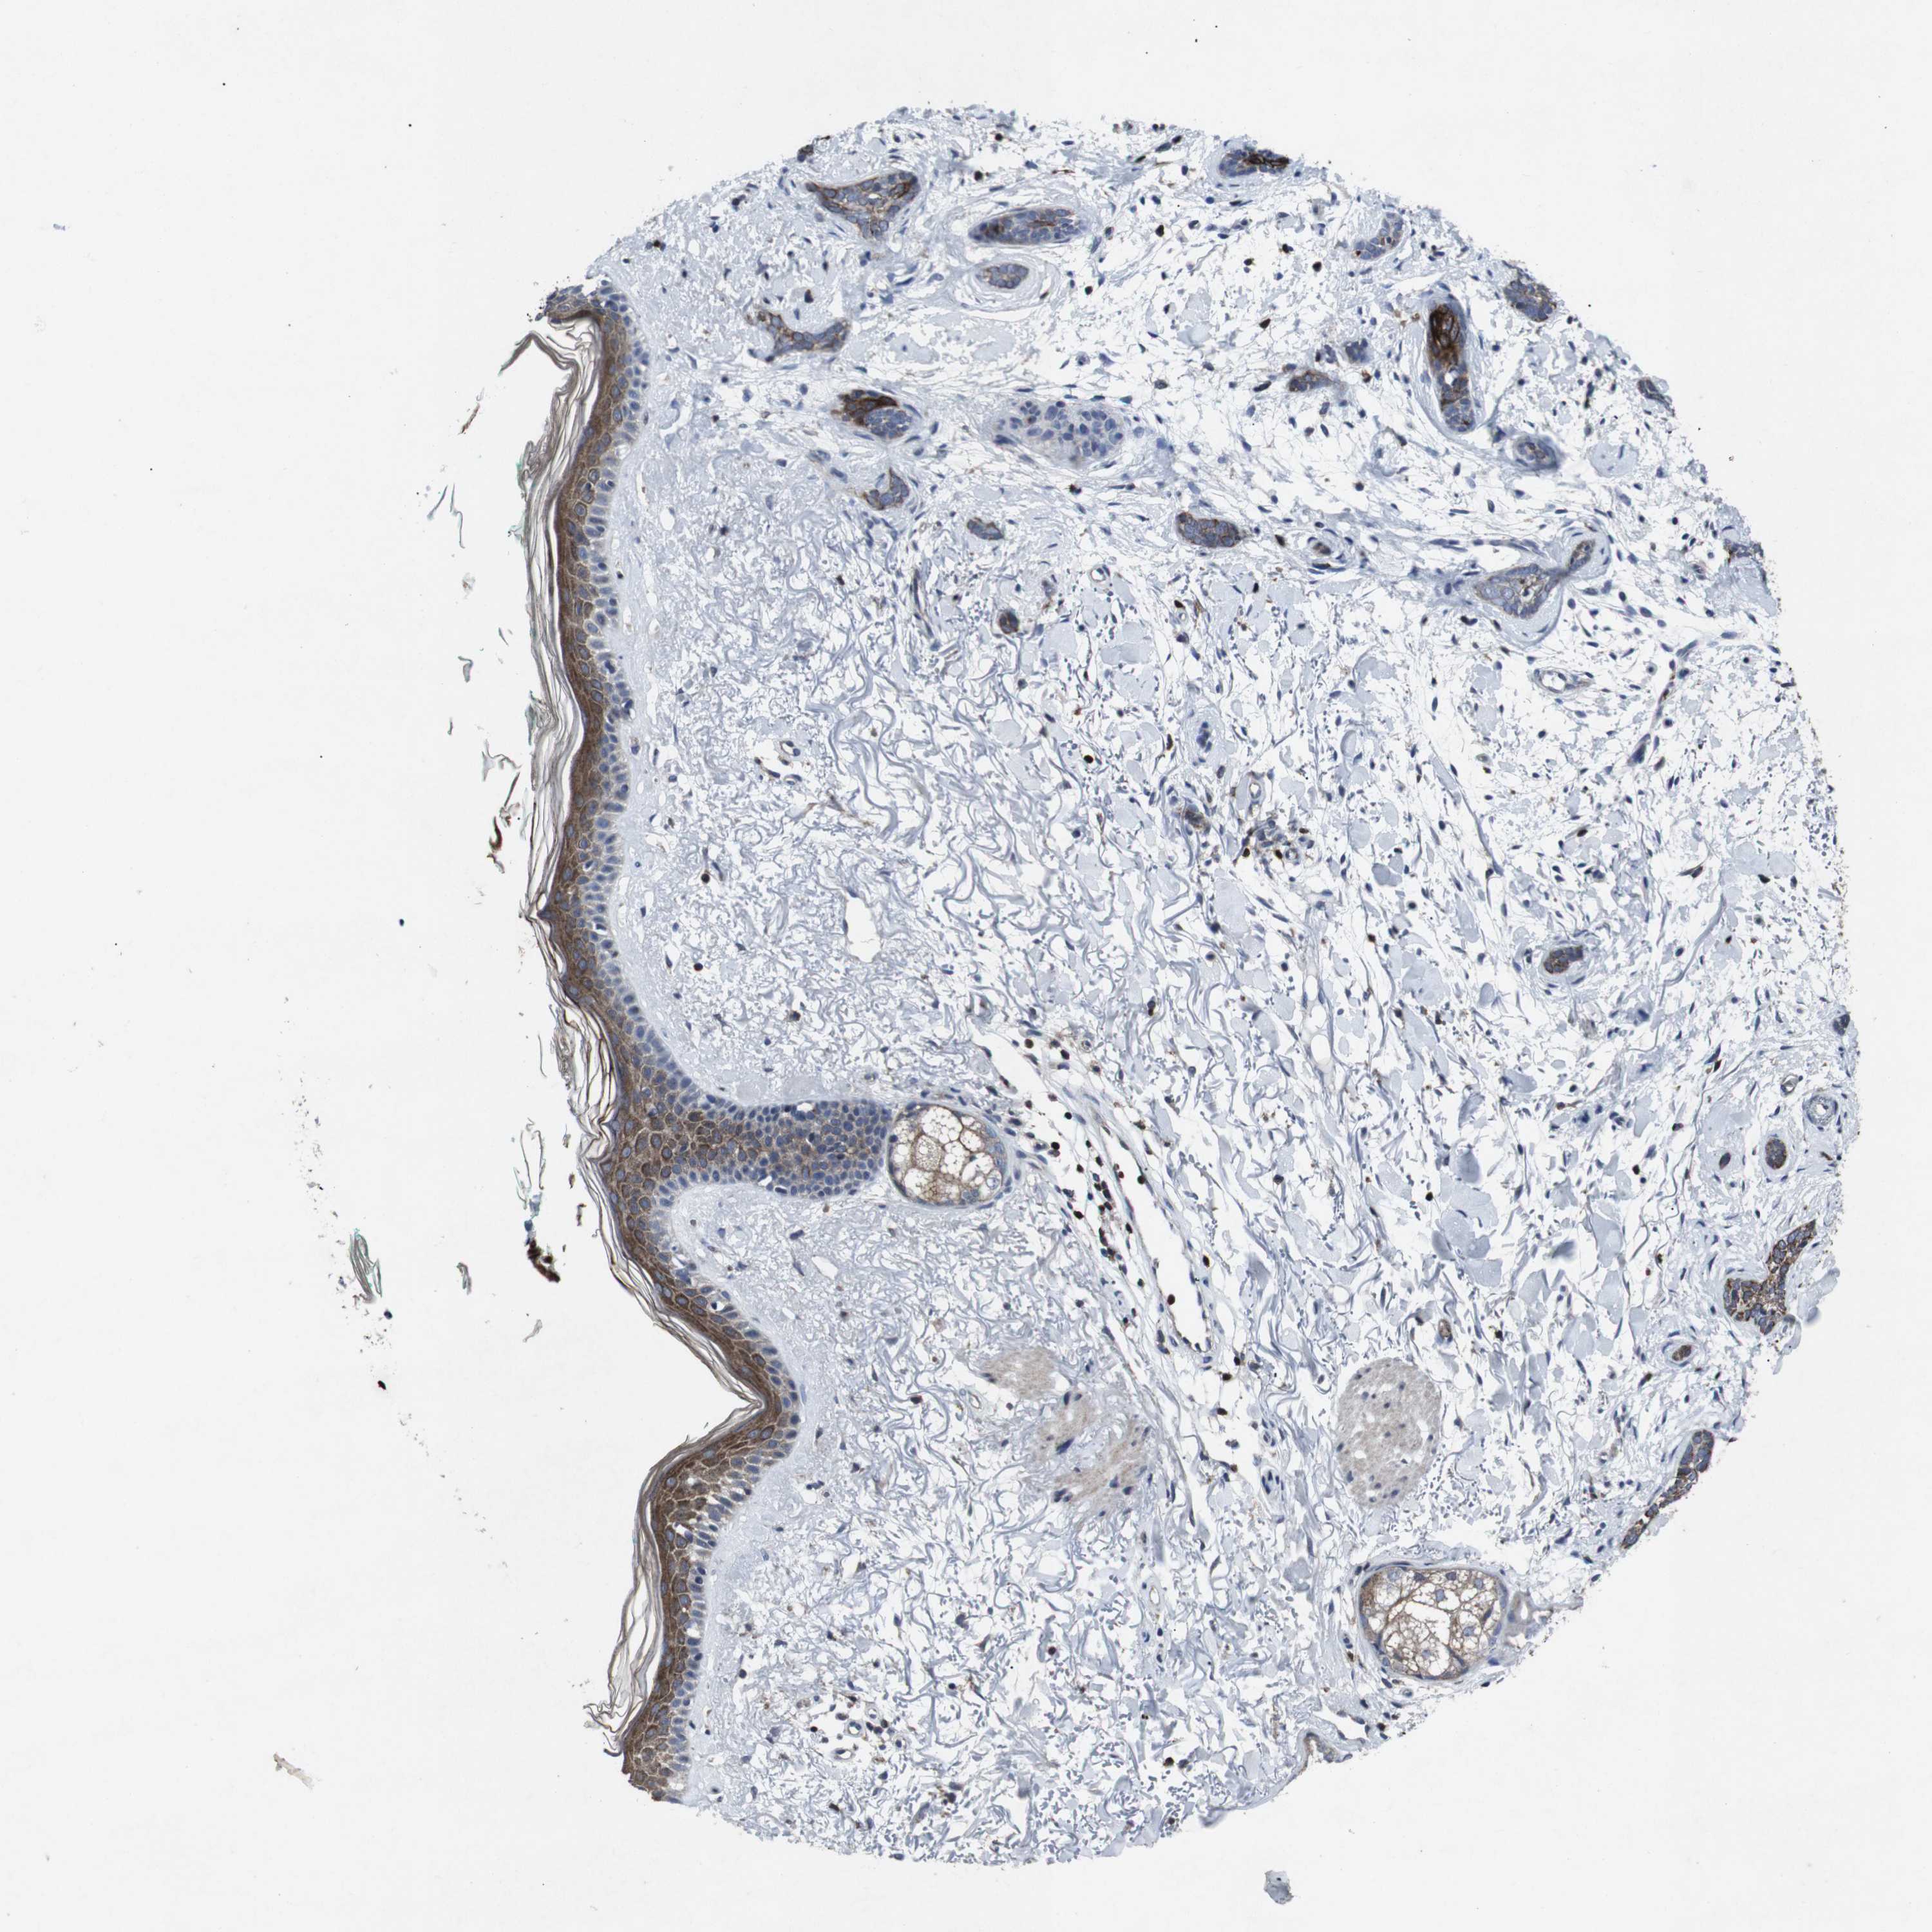

Basal cell and squamous cell cancer

SKIN CANCER - Protein expressioni

A mouse-over function shows sample information and annotation data. Click on an image to view it in a full screen mode. Samples can be filtered based on level of antibody staining by selecting one or several of the following categories: high, medium, low and not detected. The assay and annotation is described here.

Antibody stainingi

Antibody staining in the annotated cell types in the current human tissue is reported as not detected, low, medium, or high, based on conventional immunohistochemistry profiling in selected tissues. This score is based on the combination of the staining intensity and fraction of stained cells.

Each image is clickable and will lead to virtual microscopy that enables deeper exploration of all samples and also displays staining intensity scores, fraction scores and subcellular localization as well as patient and tissue information for each sample.

Antibody CAB013108

Staining

Intensity

Quantity

Location

Basal cell carcinoma

Adnexal tumor, benign